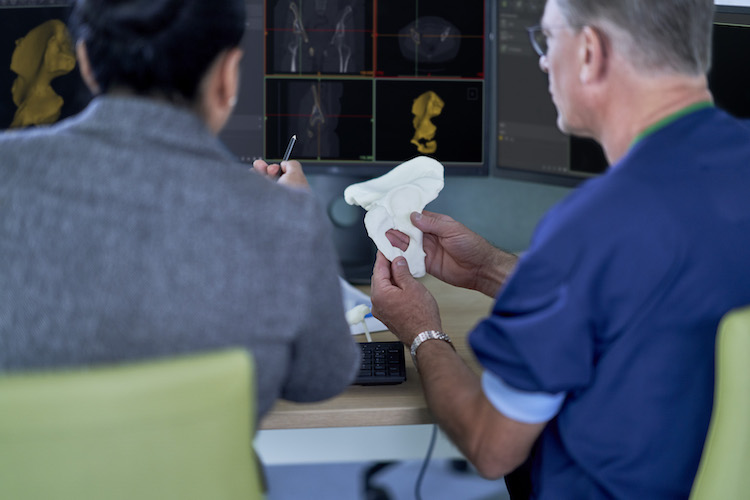

3D Printing in Medicine: Philips’ Partnerships with 3D Systems and Stratasys

Charles R. Goulding and Preeti Sulibhavi remark on Philips’ transformation into a healthcare-focused company how its engagement in 3D printing activities can help.

Materialise Enlightens Medical Care With FDA-Approved Cardiovascular Software

Materialise has received FDA clearance for its cardiovascular planning software.

Materialise Mimics inPrint Certification Program Clears Ultimaker and Formlabs for Medical 3D Printing

Materialise’s announcement today of FDA-cleared medical model 3D printing encompasses vat polymerization and material extrusion technologies in addition to PolyJet.

FDA-Cleared Medical 3D Printing with Stratasys and Materialise

3D printing medical models offers benefits to patients and those providing their care with highly accurate patient-specific anatomies able to be held, examined, and practiced on.